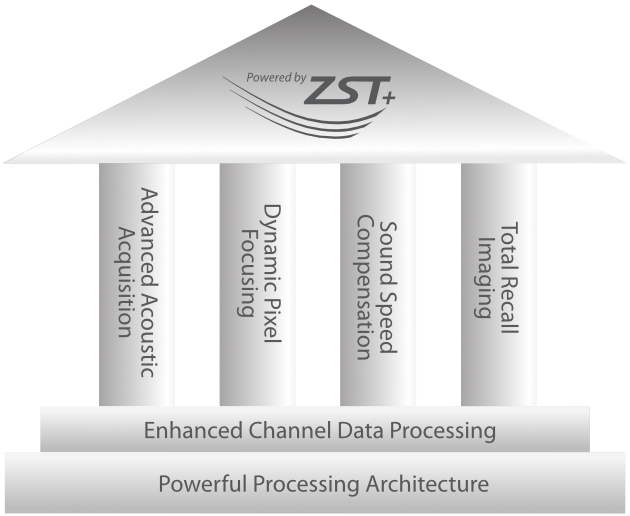

Powered by ZST +

Für die Ultraschalltechnologie stellt die ZST+-Plattform einen bedeutenden Fortschritt dar, da sie statt der herkömmlichen Strahlformung die Kanaldatenverarbeitung verwendet. Diese bahnbrechende Innovation löst übliche Zielkonflikte zwischen räumlicher Auflösung, zeitlicher Auflösung und Homogenität des Gewebes auf, woraus sich eine beispiellose Bildqualität ergibt, die den Weg frei macht für unendlich viele Bildgebungslösungen.